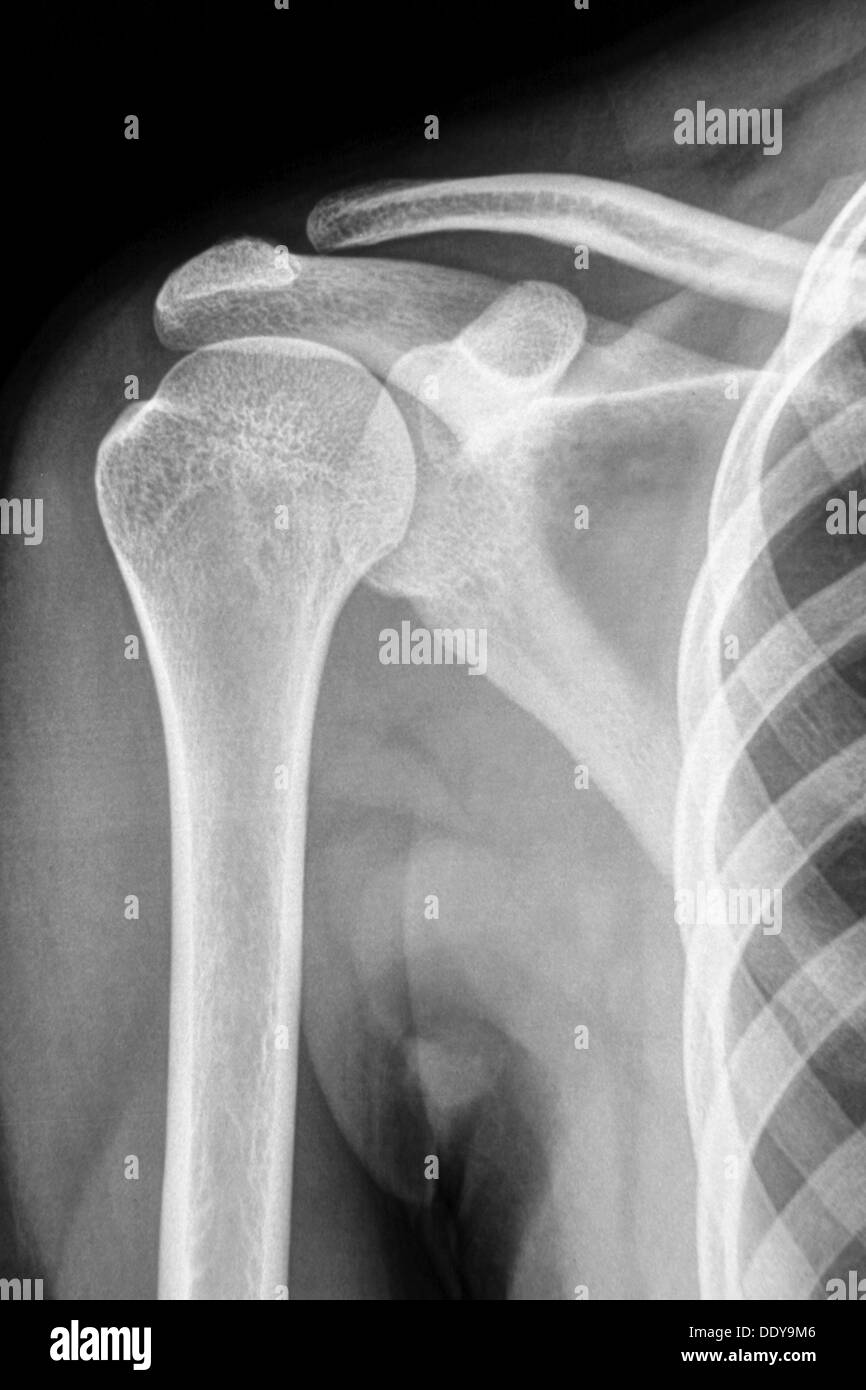

X Ray Of Arm And Shoulder . — the shoulder series is fundamentally composed of two orthogonal views of the glenohumeral joint including. The humeral head should be on the glenoid in any other. Articular surfaces should be parallel. — a normal shoulder x ray will demonstrate the bones of the shoulder to have expected normal appearance without. — glenohumeral joint.

— a normal shoulder x ray will demonstrate the bones of the shoulder to have expected normal appearance without. The humeral head should be on the glenoid in any other. — the shoulder series is fundamentally composed of two orthogonal views of the glenohumeral joint including. Articular surfaces should be parallel. — glenohumeral joint.

X Ray Of Arm And Shoulder Articular surfaces should be parallel. The humeral head should be on the glenoid in any other. — a normal shoulder x ray will demonstrate the bones of the shoulder to have expected normal appearance without. — glenohumeral joint. — the shoulder series is fundamentally composed of two orthogonal views of the glenohumeral joint including. Articular surfaces should be parallel.